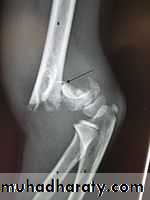

Supracondylar fracture of humerus:

Supracondylar humeral fracture in children is one of the most common fractures seen in the pediatric orthopedic clinic setting worldwide. It's a fracture that occurs at the supracondylar area or the metaphysis of the distal humerus & accounts for 65.4% of upper extremity fractures in children .There are two types of supracondylar fractures in children according to direction of displacement of distal fragment i.e. extension type (97%) and flexion (3%).X-ray of elbow joint (lat. View)

The Gartland classification is a system of categorizing supracondylar humerus fractures (extended type), clinically useful as it predicts the likelihood of associated neurovascular injury, such as anterior interosseous nerve neurapraxia or brachial artery disruption.

Type

DescriptionI

Non-displaced

II

Angulated with intact posterior cortex

III

Complete displacement